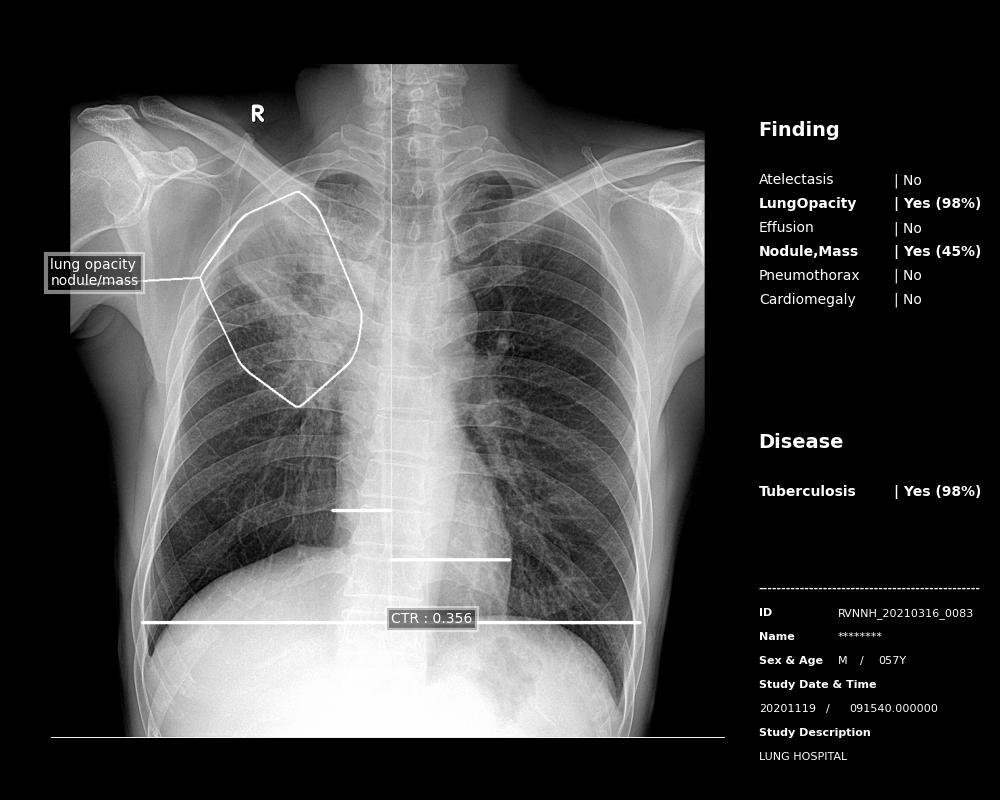

Ai Radiologist Assistant Detection

- Chest Abnormalities: Atelectasis, Lung Opacity, Effusion, Mass, Pneumothorax, Cardiomegaly, Tuberculosis, Nodule

- Diseases: Tuberculosis, Pneumonia

- Lesions: Contour Plot, Heat map, Bounding Box

- Others: Cardiothoraxic Ratio